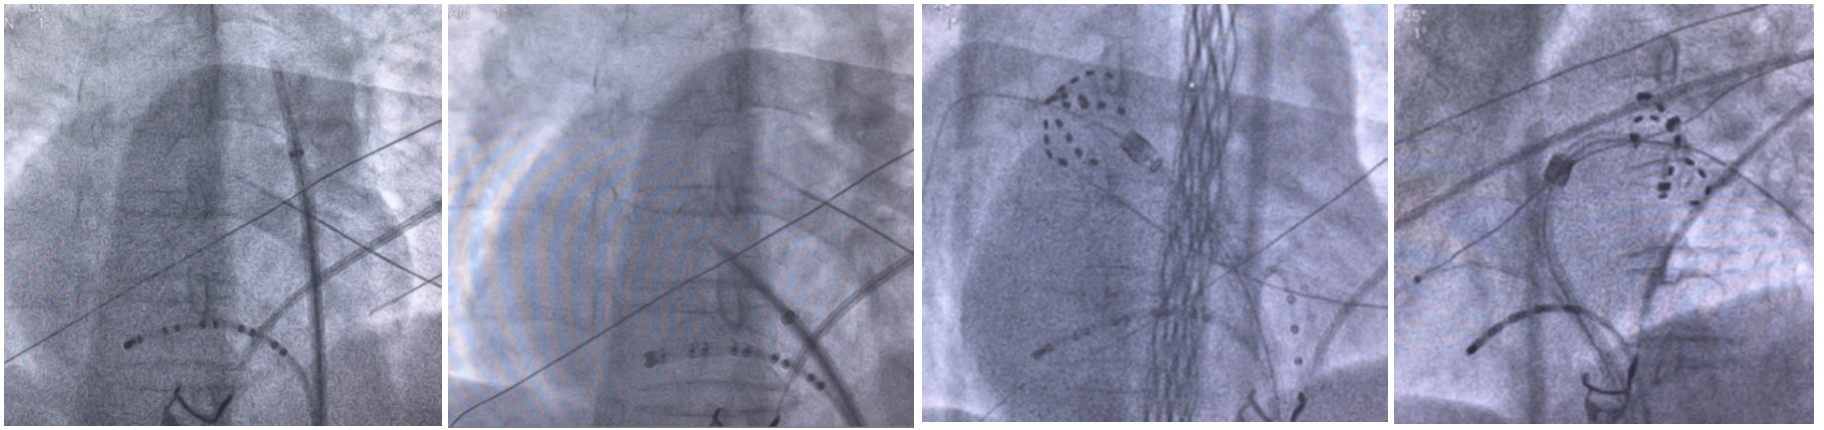

图 5 左 1 左 2 为房间隔穿刺过程;右 1 肺右上肺静脉花瓣状消融;右 2:左上肺静脉网篮状消融